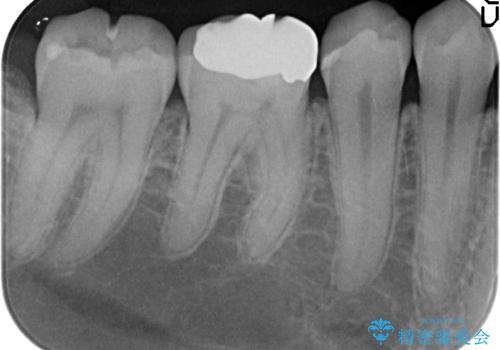

- 右下5番目の歯がしみるので診て欲しいといらっしゃった方の症例です。

虫歯を除去後、セラミックインレーによる修復を行いました。

虫歯治療は虫歯の進行度によって処置が変わってきます。

虫歯が小さければ、インレー・クラウン等による修復・補綴処置を行うだけで済みます。

しかし虫歯が大きくなると神経処置や抜歯等をしなければならない場合もあります。

ですので虫歯治療においては早期発見・早期治療が肝要です。